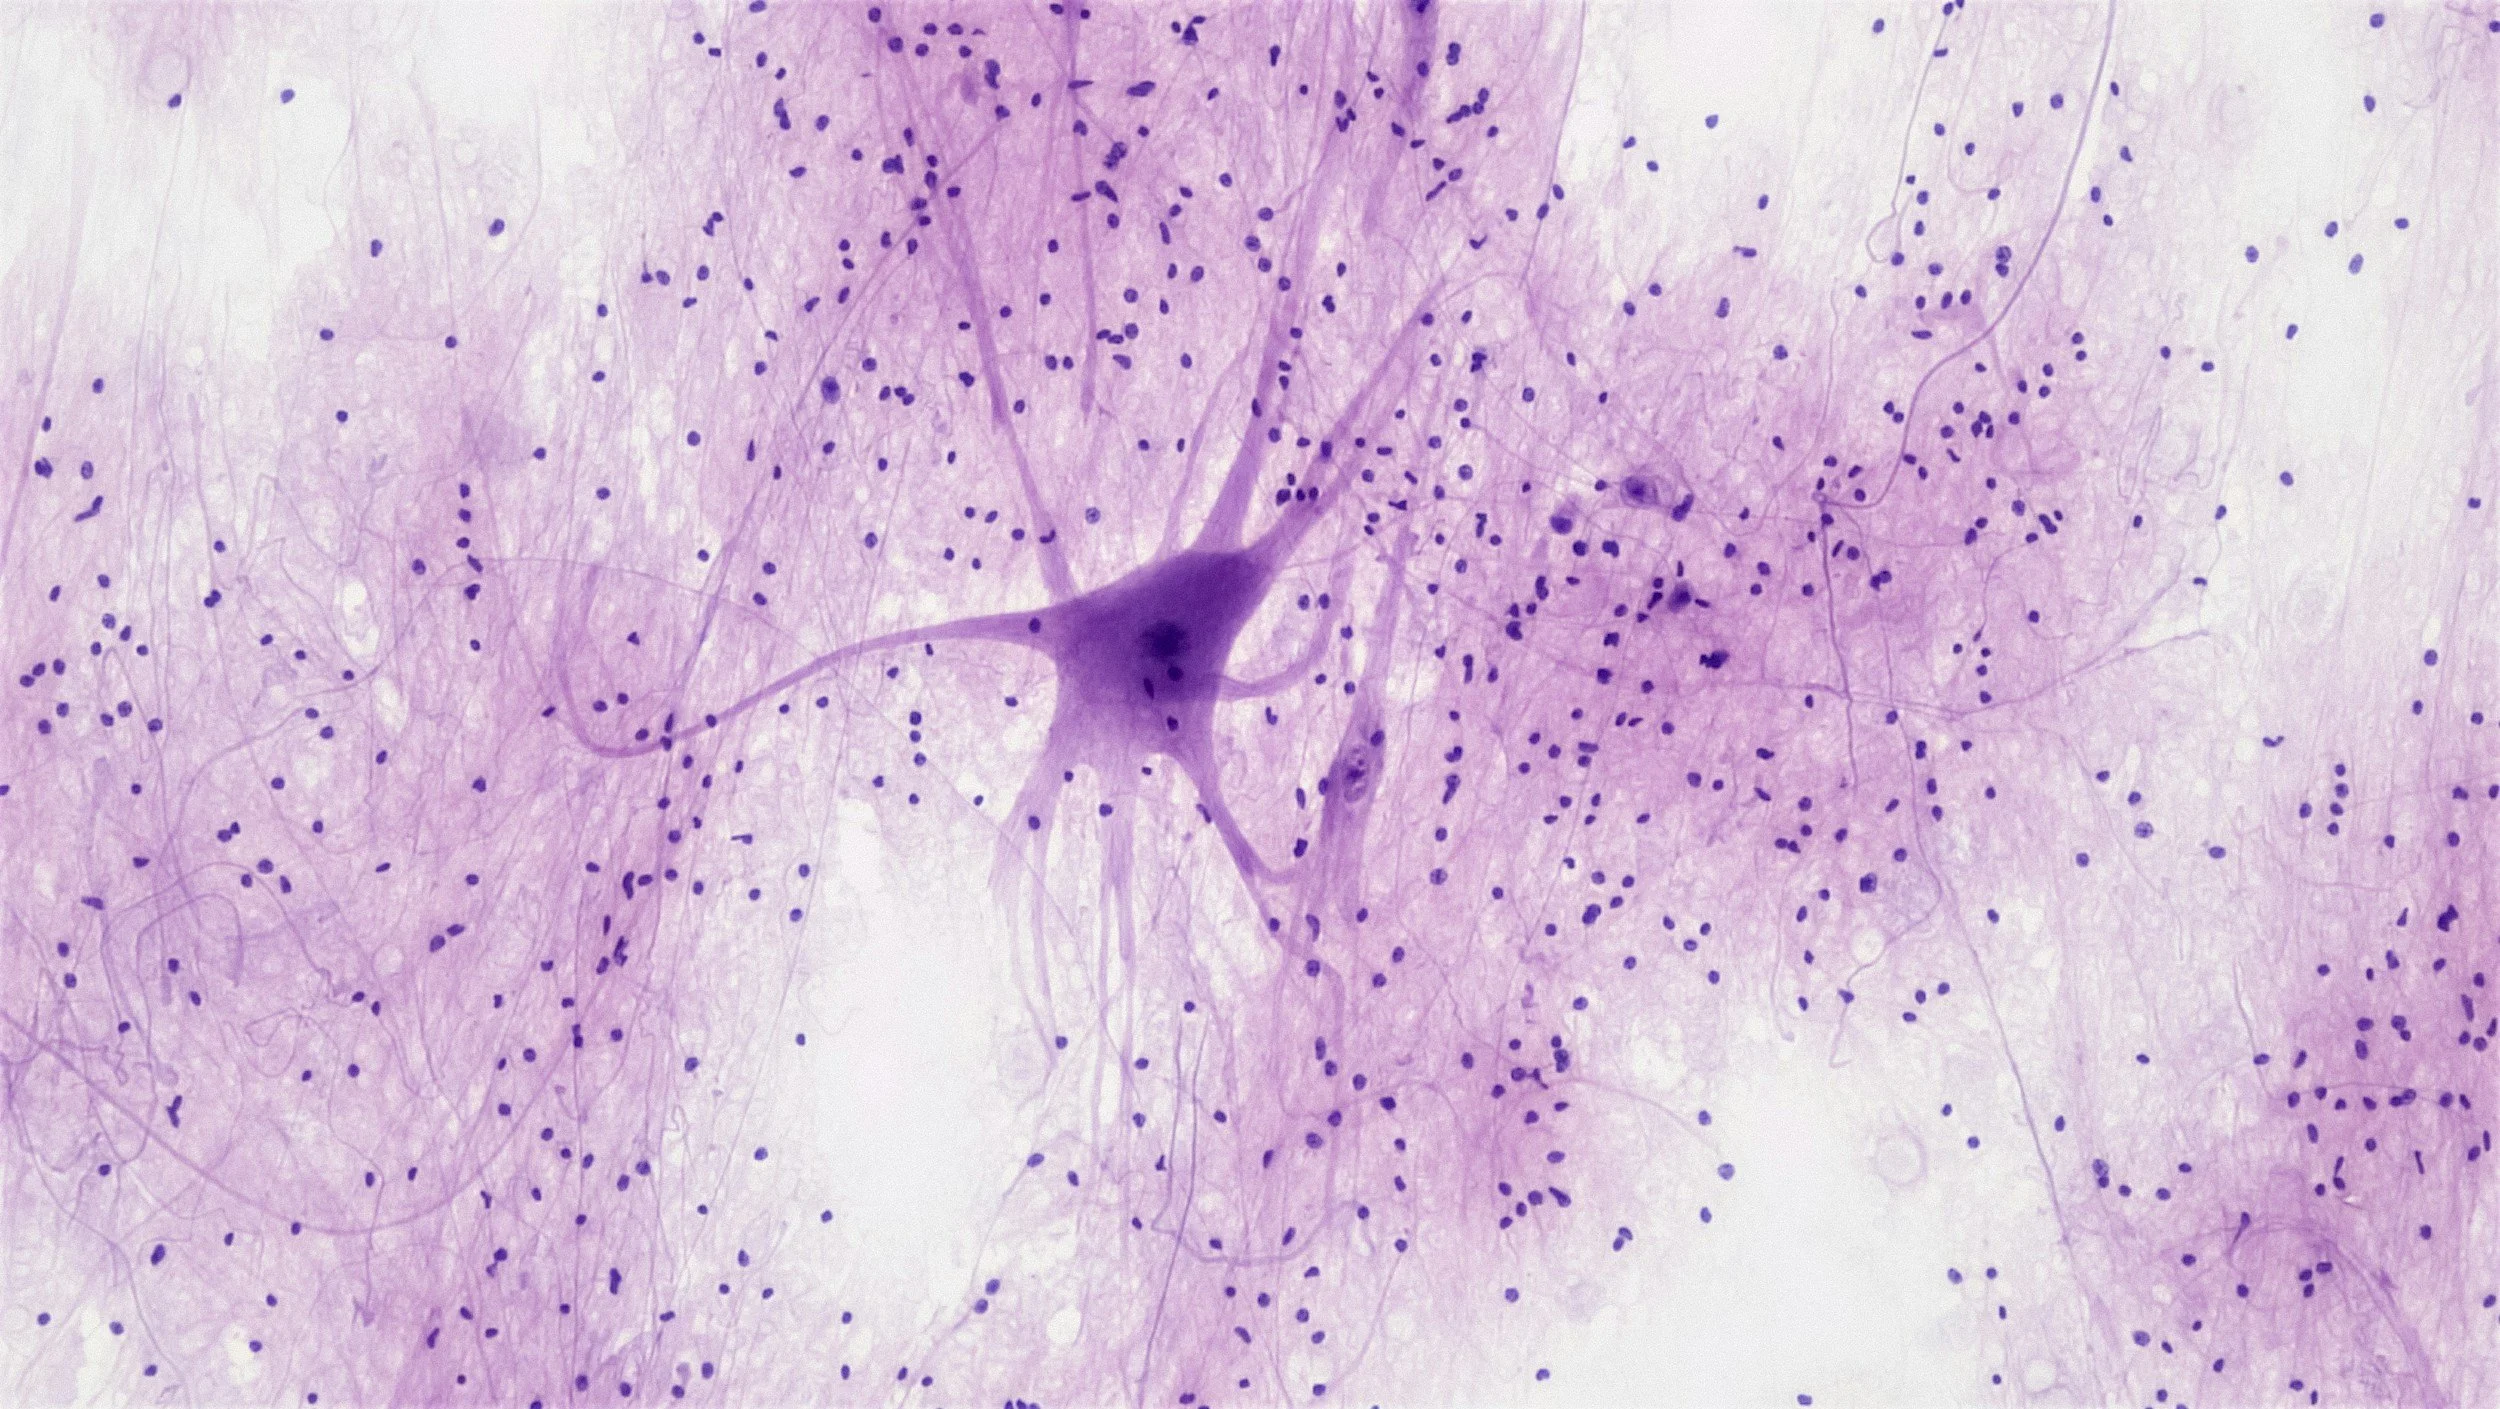

The Kam lab is focusing on neuronal and non-neuronal mechanisms of pathogenesis of neurodegenerative diseases including Alzheimer’s and Parkinson’s disease. We are trying to understand the molecular mechanisms of neuronal cell death as well as to identify the role of microglia-astrocyte axis in neurodegeneration. We are looking for identifying novel targets that are essential for pathogenesis of neurodegenerative diseases and developing disease-modifying drugs targeting key molecules.

Molecular mechanisms of neurodegeneration and neuroinflammation in neurodegenerative diseases.